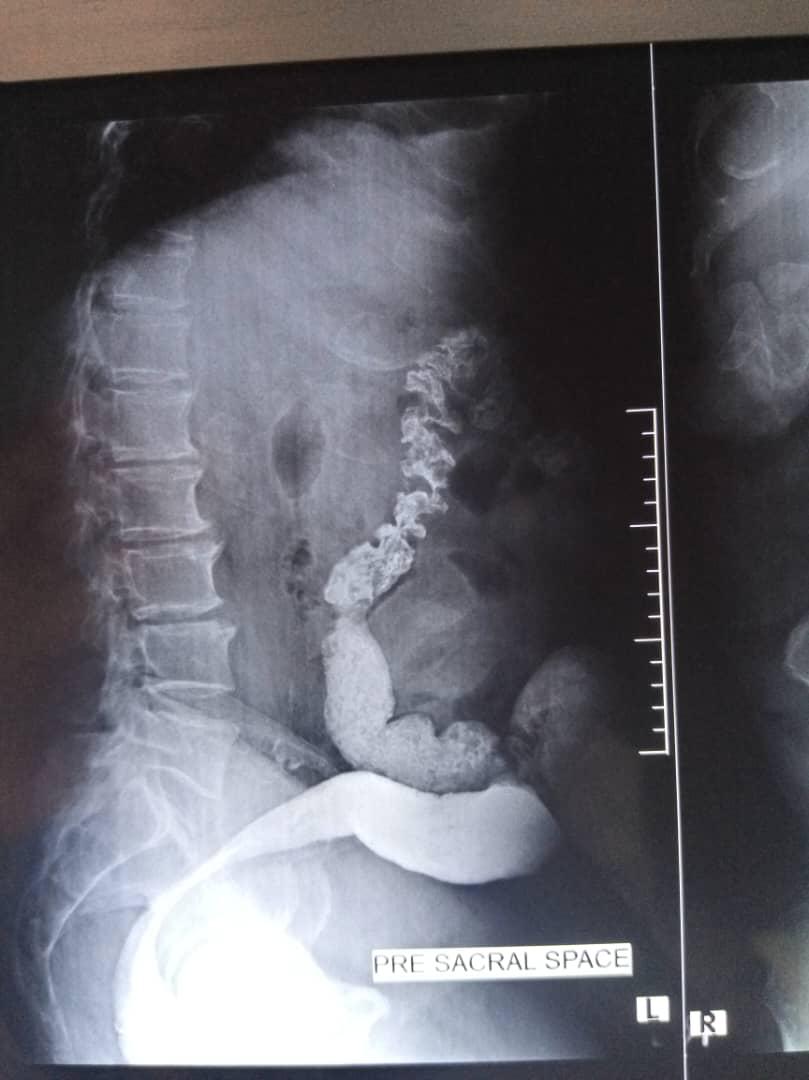

Barium enema examination